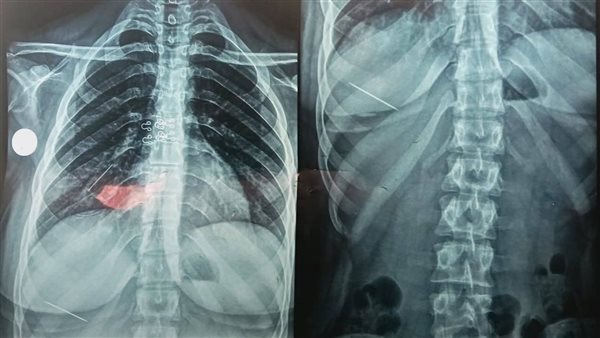

وتحت إشراف الدكتور محمد فهمي النعماني عميد كلية الطب ورئيس مجلس إدارة المستشفيات الجامعية، حضرت المريضة إلى قسم الطوارئ وهي تعاني من ألم شديد بالصدر وسعال مستمر وضيق في التنفس، وعلى الفور، أُجريت لها الفحوصات الطبية والآشعة اللازمة، والتي كشفت عن وجود دبوس معدني داخل الشعب الهوائية، إضافة إلى دبوس آخر في البطن.

وقرر الفريق الطبي برئاسة الدكتور أحمد عامر خميس أستاذ الأمراض الصدرية، إدخال المريضة إلى غرفة العمليات، حيث تم إجراء منظار شعبي مرن تحت التخدير، وتم استخراج الدبوس بنجاح مع المتابعة الدقيقة للحالة حتى استقرارها.